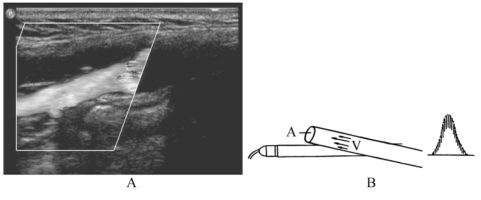

(1)血流性质:正常心腔及血管内血流为层流,红细胞平行向前运动,由于血液黏性,血管中央速度略快于近壁处血流速度。彩色多普勒显示纯红色或蓝色血流。中央色泽较明显,边缘略暗(图1-13A)。频谱多普勒显示窄带(血流速度分布范围小)、空窗(频谱与基线间的空隙)型(图1-13B)。异常血流为湍流,彩色多普勒显示多彩镶嵌血流(图1-14A),脉冲多普勒呈宽频带或充填型单向或双向湍流频谱(图1-14B)。

图1-13 正常血流多普勒成像图

A.彩色多普勒正常血管内呈纯红色伪彩为层流;B.正常血管内层流血流频谱(空窗型)